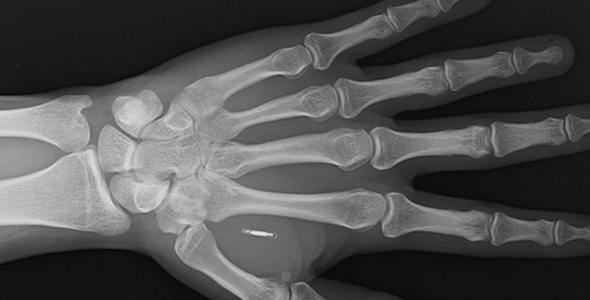

悠仁s/悠子sが反逆し脱走したら両親は一瞬で失脚 体内にチップが埋め込まれているかも